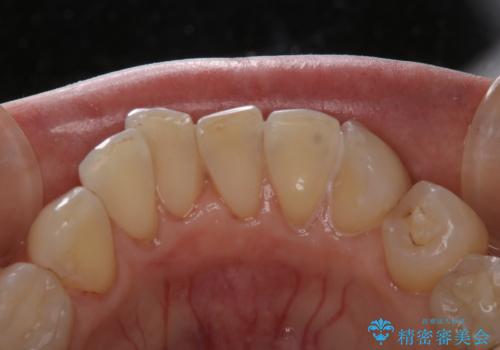

1年ぶりにコーヒーによる着色落とし PMTC